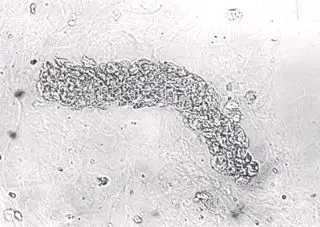

1)形态:管形中的红细胞常互相粘连而无明显的细胞界限,有的甚至残缺不

背景中可见较多的因染色而溶血的红细胞.